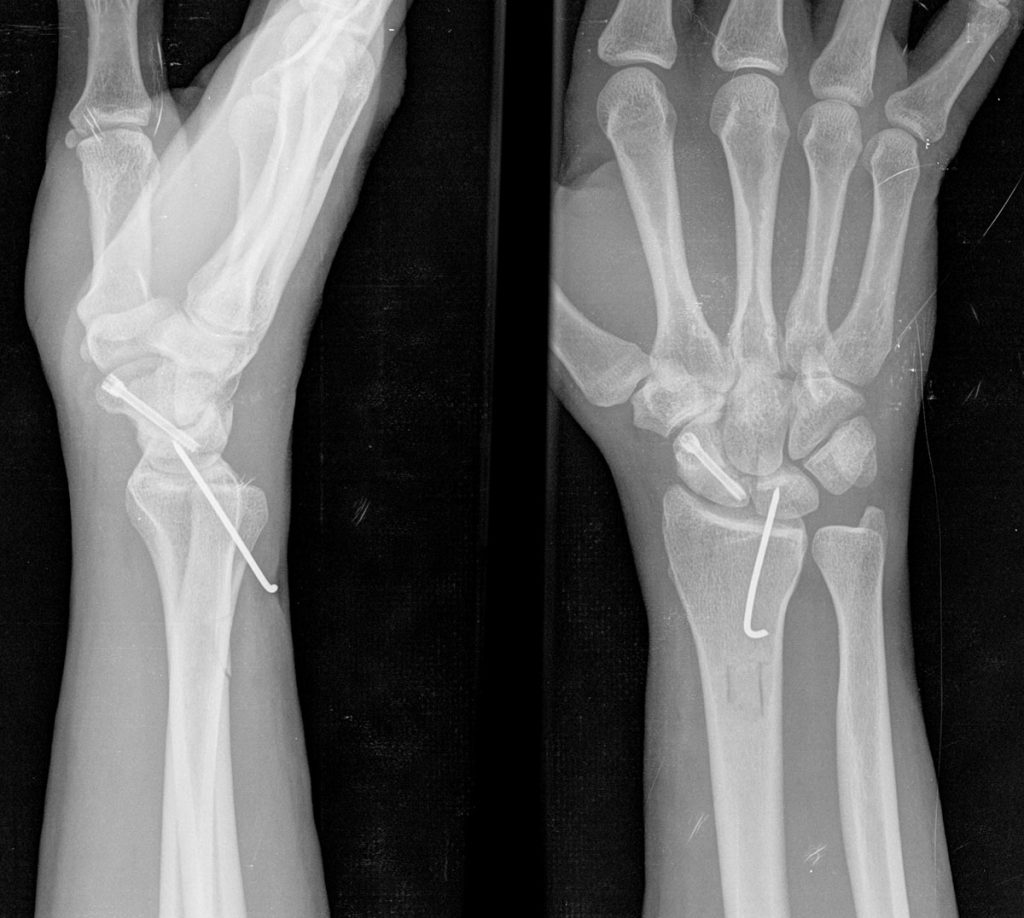

Los objetivos del tratamiento son calmar el dolor, conseguir la mejor funcionalidad de la muñeca y mano posible y prevenir la artrosis.  Generalmente, es necesario el tratamiento quirúrgico para limpiar y legrar el foco de la fractura para poder poner algún tipo de injerto óseo y estabilizar la fractura con agujas o tornillos (Figura 3).  Dentro de las opciones quirúrgicas se incluyen también la estiloidectomía del radio, la carpectomía proximal, le extirpación del escafoides y artrodesis o fusión parcial de la muñeca (Figura 4) e incluso la artrodesis o fusión total de la muñeca, dependiendo entre otras cosas del grado de degeneración artrósica de la muñeca asociada a la pseudoartrosis.

PATOLOGIAS MUÑECA - PSEUDOARTROSIS DE ESCAFOIDES Figura 4 - Fusión parcial de la muñeca. Artrodesis 4 esquinas

Figura 4 - Fusión parcial de la muñeca. Artrodesis 4 esquinas.